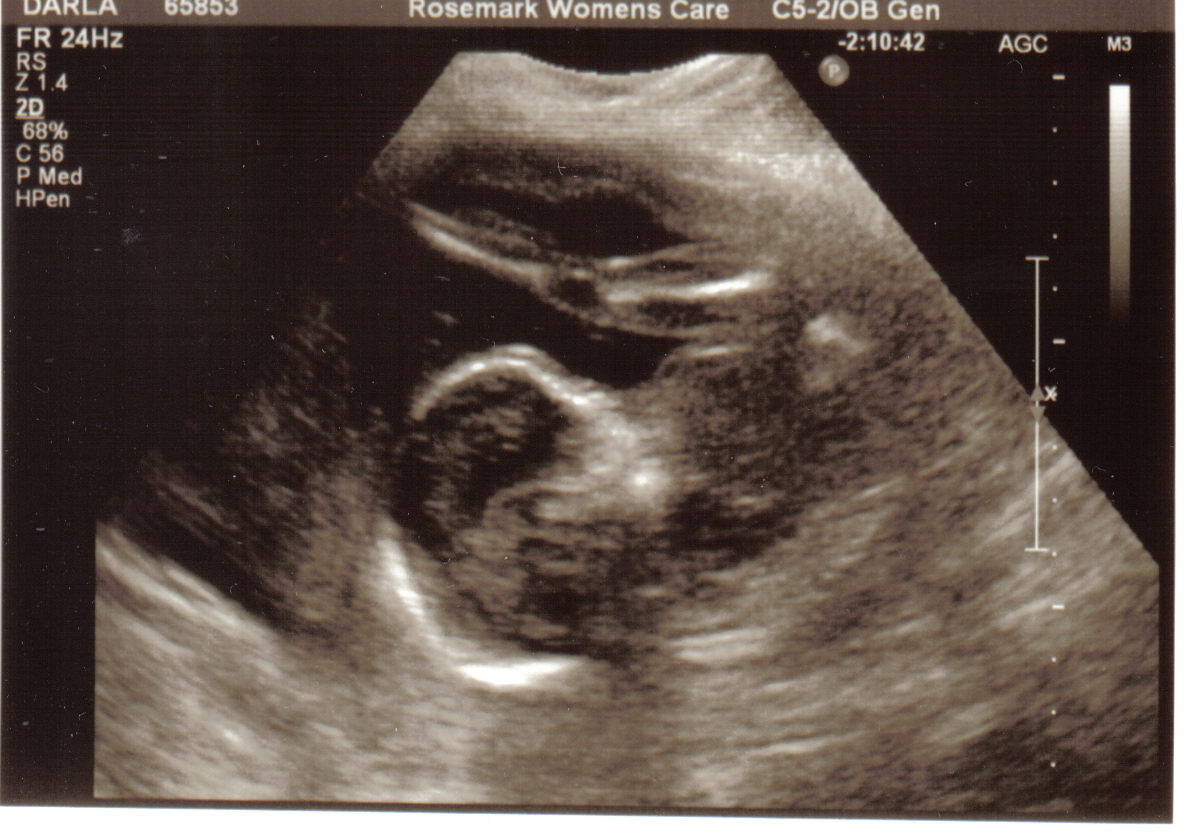

This is showing his body and his legs are stretched in front of his face